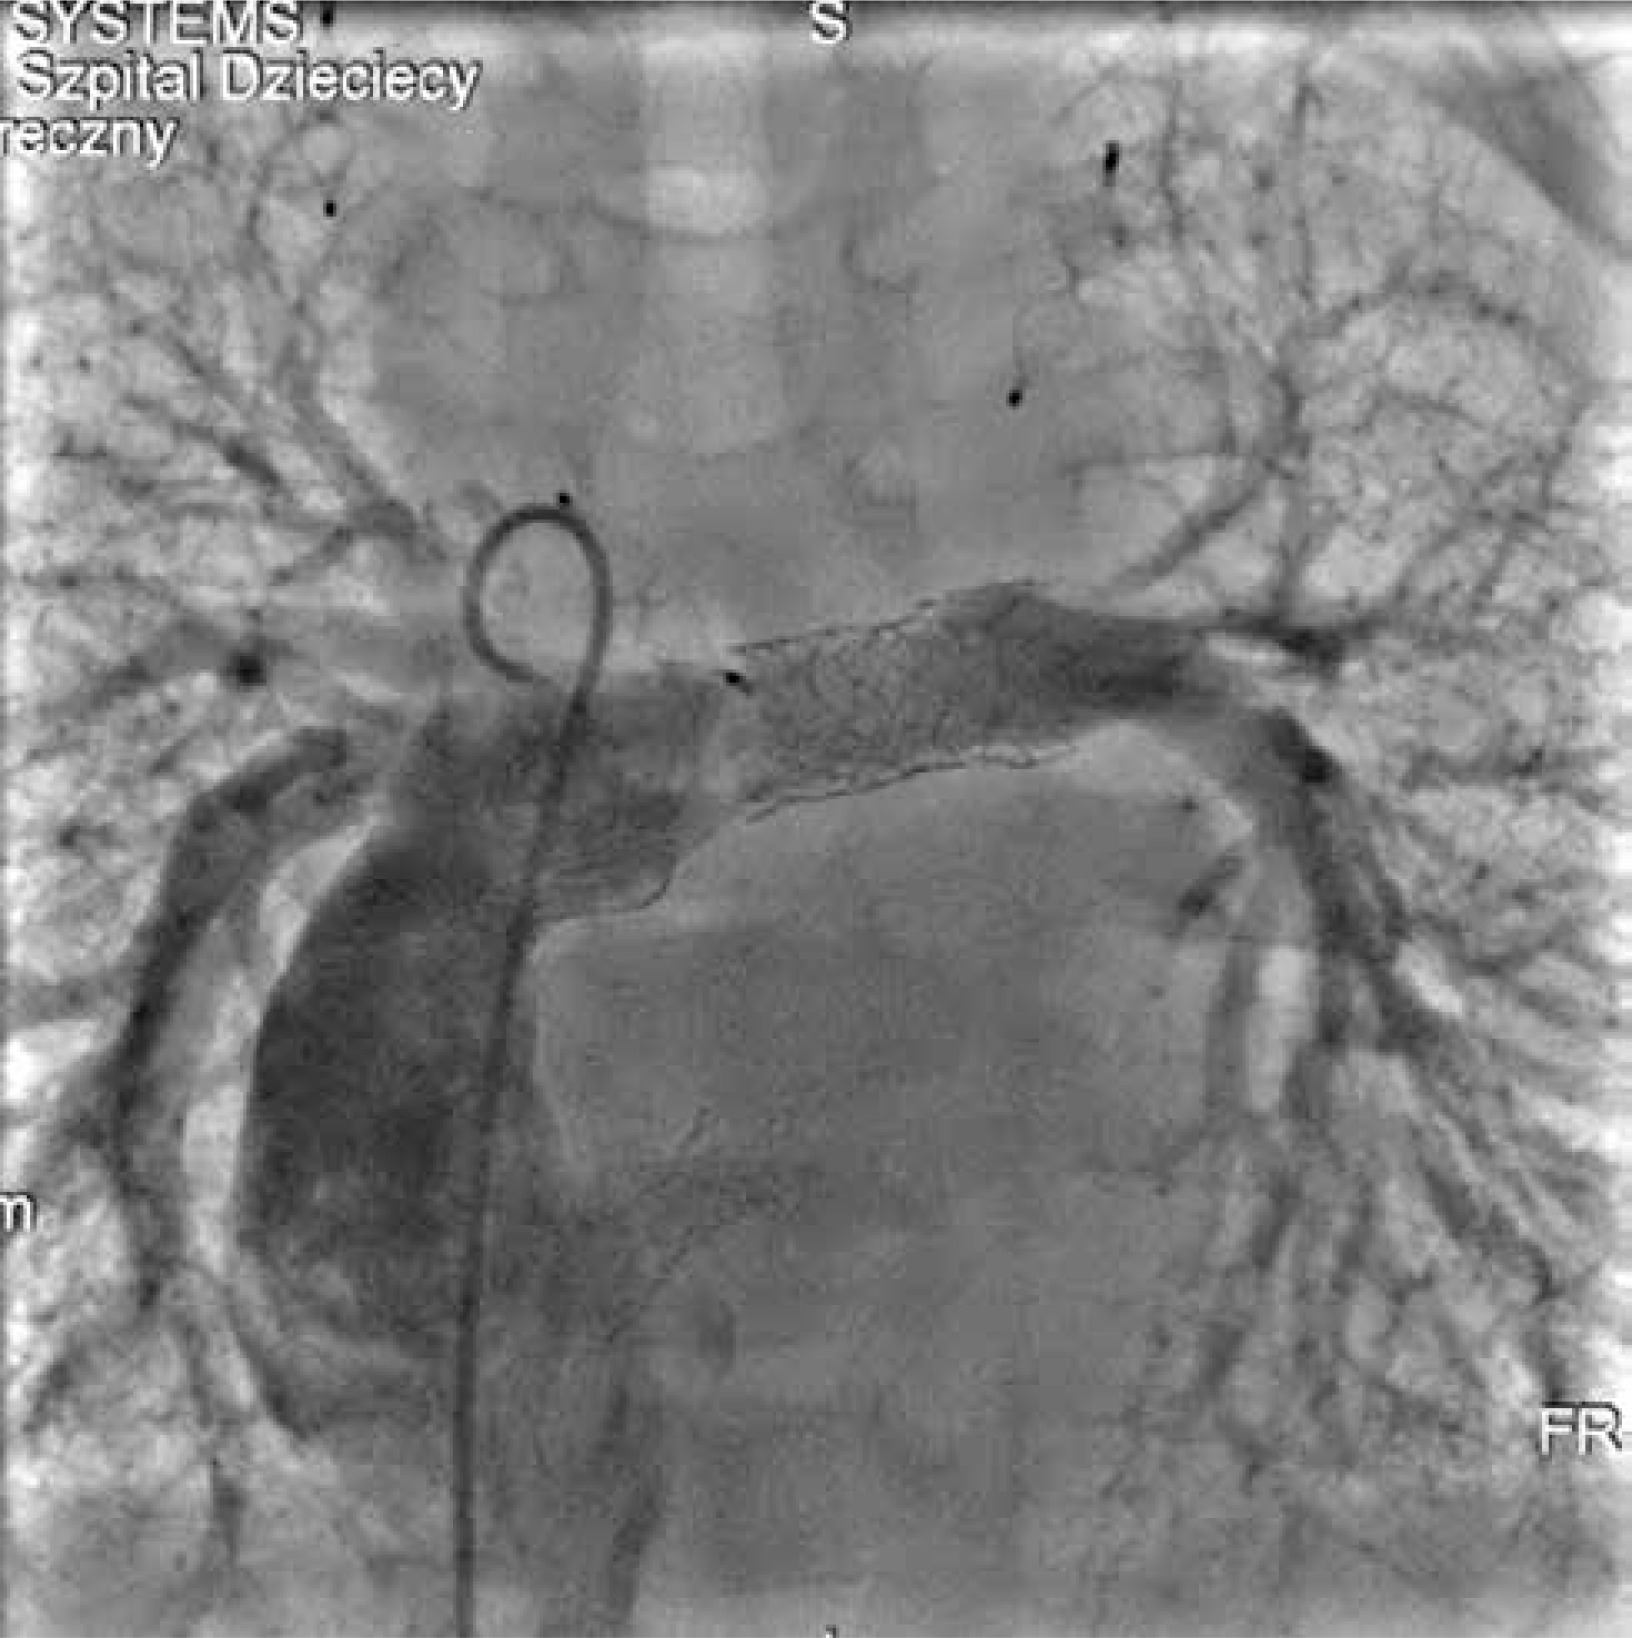

Cardiac catheterisation revealed a significant collateral vessel from the left inferior thyroid artery supplying the left lung and additional collateral vessels arising from the left (LIMA) and right (RIMA) internal mammary arteries supplying both lungs (Figure 1). The Fontan tunnel measured 14.1 mm at its junction with the IVC, widening centrally to 26 mm, and tapering to 10.9 mm at the junction with the pulmonary arteries. No fenestration was identified. The stent in the left pulmonary artery measured 9.8 mm proximally, increasing to 11.2 mm distally (Figure 2). During the procedure, an Amplatzer Vascular Plug successfully occluded the collateral vessel from the left inferior thyroid artery to the left lung, and vascular coils were placed in the RIMA and LIMA. Additionally, a 6-mm Valeo stent was implanted to create a new fenestration (Figure 3).

Figure 1

Angiogram of the left brachio-cephalic vein. The plug is inserted into the left mammary artery. Wide left brachio-cephalic artery (innominate artery), and the collateral vessel to the left lung (asterisk) are visible. A stent was placed in the left pulmonary artery